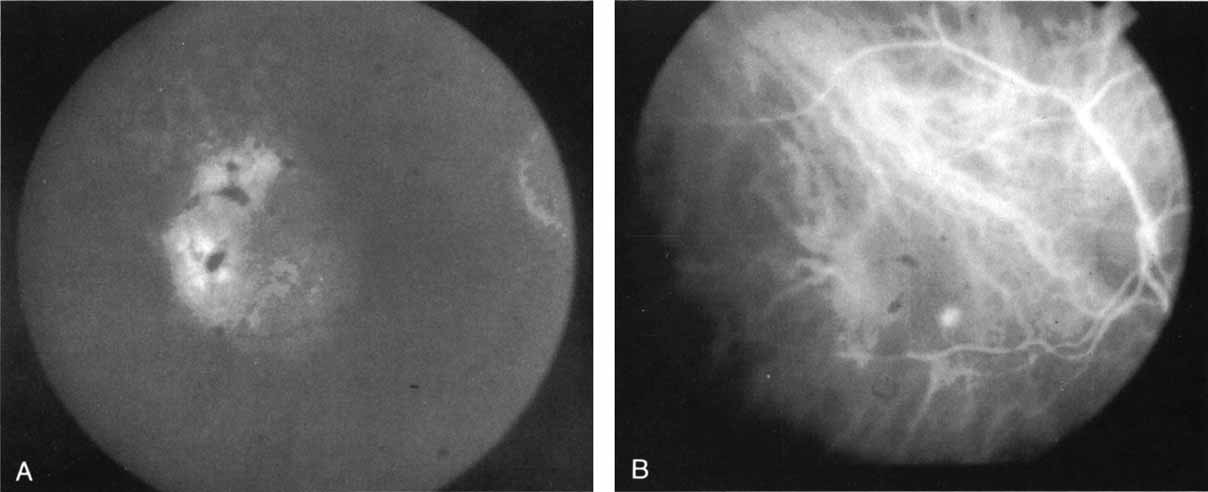

In multiple evanescent white dot syndrome (MEWDS), the typical fluorescein appearance in the acute phase of the disease involves early-phase hyperfluorescence of dots in a ring formation, corresponding to the clinically evident lesions.60 In general, these dots are found only in the posterior pole. Interestingly, ICG angiography reveals an increased number of lesions beyond those clinically evident. The angiogram initially reveals a stellate pattern of hypofluorescent spots in a ring formation.61 In the later phases of ICG angiography, however, there are more widely distributed areas of hypofluorescent spots, frequently extending far into the periphery (Fig. 15).

Fig. 15 A. Composite montage of the ICG angiogram in a patient with multiple evanescent white dot syndrome (MEWDS). Note the numerous large hypofluorescent spots with overlying smaller hypofluorescent dots. These lesions evident on the ICG study far outnumbered the clinically apparent ones. The arrow demonstrates the area that was enlarged in B. B. An interesting finding on the ICG corresponds to these areas of relative hyperfluorescence of the choroidal vessels, which indicate a localized inflammatory reaction.

The widespread nature of these lesions would help to explain the generalized nature of this condition, which is exemplified by abnormalities frequently detected in electroretinographic testing.62 In addition, some patients with MEWDS have been reported60,63 to have blind-spot enlargement on visual field testing. This was unexplained by either clinical or fluorescein angiographic examination and was attributed to an idiopathic peripapillary retinal dysfunction. ICG angiography in some of these patients has revealed confluent areas of hypofluorescent spots surrounding the optic nerve64 (Fig. 15A). This may provide the first evidence of a region of hypoperfusion or inflammation that may lead to secondary dysfunction and blind spot enlargement. It has been shown that resolution of the enlarged blind spot and return of vision does not correlate completely with the disappearance of hypofluorescent areas on ICG angiography; these lesions often remain visible on ICG study. These findings suggest that MEWDS may result in persistent abnormalities in choroidal circulation, even after vision has been restored.